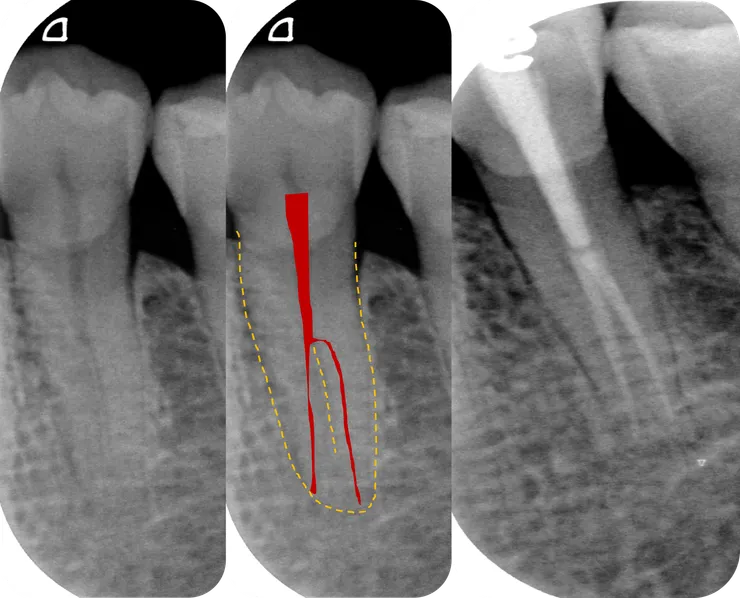

除此之外,deep split canal 發生在 lower-premolar 時,還有一個惡名昭彰的特徵,那就是如中圖紅色區域所示的 "h 形分岔"!

Shaping 大致完成後長這樣:

左下較黑處是個 ledge.

綠色箭頭所指的白洞是 buccal canal.

紅色箭頭所指的是 #10 C-pilot 彎進 lingual canal 的樣子。

這是修形完成後的樣子。

橘色箭頭指的是修掉 h 形分岔入彎處外側上方齒質後的樣子。

黃色箭頭指的是修掉卡住 file 的冠部齒質後的樣子。

修掉這兩處齒質後,NiTi rotary file 才得以順利地進入 lingual canal 修形,最後兩個 canal 都擴大到 PTG F1.

RCF 時一樣先 fil 困難的 lingual canal, 燙到分岔處後,再 fil buccal canal.

如右邊 X 光片所示,這顆的 common canal 擴得夠大可以同時放進兩支 PTG F1 GP.

對照之下可以看得出來橘色箭頭所指的那個 h 形直角分岔處被整個修平了。

順利地 RCF.